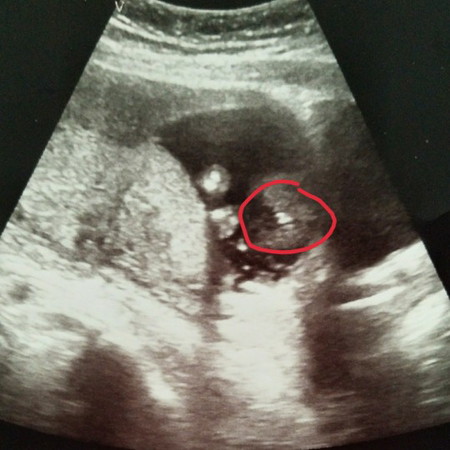

แม่ๆๆท่านไหนพอจะมองออกบ้างใยค่ะว่าเป็นเพศอะไรเอ่ย..พอดีไปซาวด?คุณหมอบอก ผุ้ชาย 80/ ค่ะแต่ไม่ชัดเจน แม่ๆๆท่านไหนพอมองออกมั้ยค่ะว่าเป็น หญิงหรือชายค่ะ